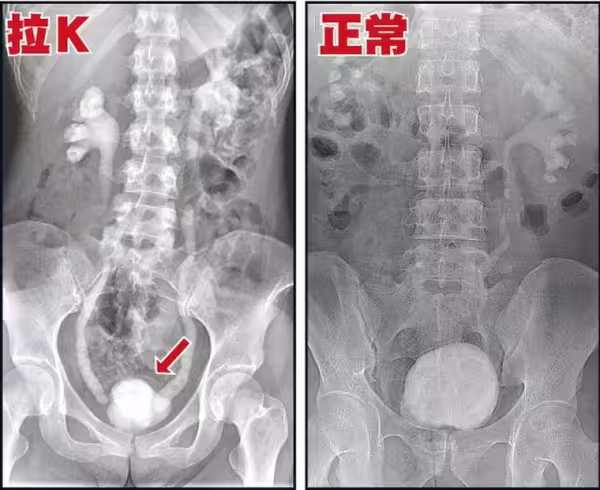

高雄16歲女高中生「只因這東西就終生包尿布」!醫師嘆氣:一輩子沒救了!一定要轉出去,爸媽千萬注意孩子的舉動!

其實吸食K他命長久的人,必然會有這種尿頻、尿急、尿痛的症狀,

這是由於K他命的獨特性,持續傷害人體的泌尿系統,導致的嚴重後果。

K他命是一種結晶、有稜角的固體物質,

從鼻子吸入,然後進入呼吸系統、消化系統,

其中約有5%的K他命原型會經泌尿系統的尿道排出。